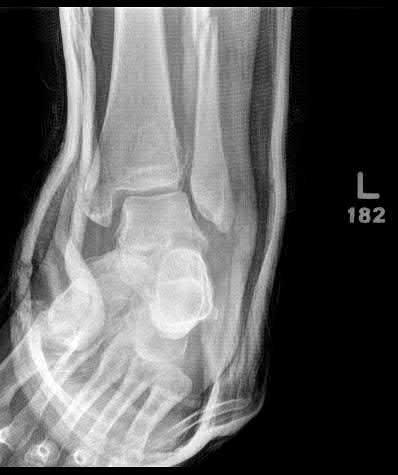

A 25-year-old female is involved in a motor vehicle collision. She presents with the isolated injury seen in Figures A through D. Her leg is swollen but her skin is intact. She has no clinical signs of compartment syndrome. Which of the following treatment options will allow for maintenance of fracture alignment and minimize the risk of soft tissue complications?

The patient presents with a closed distal third metaphyseal-diaphyseal distal tibia fracture with simple intra-articular extension. Immediate intramedullary nailing along with percutaneous fixation of the articular component provides appropriate restoration of length, rotation and alignment and minimizes the risk of wound complication.

Displaced distal third tibia fractures may be associated with simple intraarticular extension. Operative treatment of intra-articular distal tibia fractures has historically been performed with open reduction and internal fixation. Early open reduction and plate fixation of pilon fractures has been associated with high rates of infection and wound complication. In select patterns with simple articular extension, percutaneous screw fixation and medullary nailing may provide appropriate reduction with minimal soft-tissue risk.

Figures A and B demonstrate a distal third tibial shaft fracture with simple intra-articular extension. The axial and coronal CT cuts in Figures C and D further clarify the articular injury. Illustrations A and B demonstrate a comminuted distal third tibial fracture with simple intra-articular extension. Illustrations C and D are fluoroscopic images of the same injury after intramedullary nailing and percutaneous fixation of the articular component.